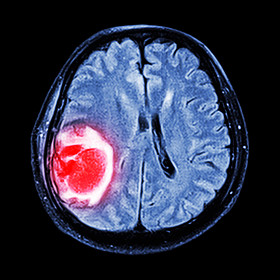

磁共振脑: 显示大脑右顶叶脑肿瘤

图司机为设计师提供高清磁共振脑: 显示大脑右顶叶脑肿瘤图片版权下载,图片为科学技术,大小为4.35MB,尺寸为3407 x 3407px,更多关于图像,蓝色,背景,隔离,リボンとユーロ,人类,人,健康,头,医学,保健服务,医疗,文家,黑色,猫,博士,医院,病人,治疗,疾病,显示,癌症,电影,雷,权利,生病,在,头骨,大众,为,的,诊断,解剖,大腦,x 光,手术,扫描,放射学,X 射线,颅骨,神经病学,肿瘤,叶,磁共振成像,大脑,麻痹,ct,神经外科,顶叶,神经,癌,转移,脑波机商用高清版权图片,快来图司机免费下载吧。